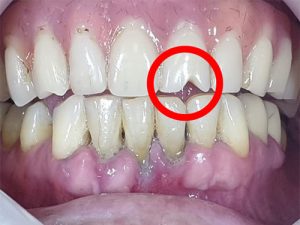

The patient, in her forties, complained of bad breath.

Teeth 32, 31, 41 and 42 presented with periodontitis with deep pockets and mobility, which required extractions, hence the choice of immediate loading.

In addition, tooth 21 in the upper arch was visibly worn, as was the proximal-incisal area between teeth 32 and 31, typical signs of a passionate fondness for hard foods to grind, such as sunflower seeds, roasted corn, etc…